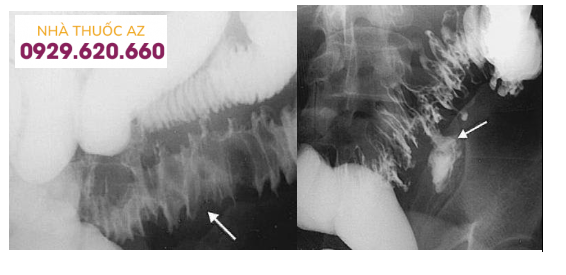

1.Chụp đại tràng cản quang

Chụp đại tràng cản quang từng được xem là tiêu chuẩn vàng để chẩn đoán VTTĐT. Đặc điểm của túi thừa trên hình ảnh X-quang là một ổ đọng thuốc xuất phát từ thành đại tràng.

Kích thước túi thừa có thể to nhỏ khác nhau, từ vài mm đến vài cm. Lòng đại tràng (ĐT) chứa túi thừa thường có hình ảnh hẹp đồng tâm, và niêm mạc hình răng cưa do lớp cơ vòng và cơ dọc dày lên.

Chú thích ảnh trái: Mũi tên chỉ hình ảnh phù nề thành đại tràng trong VTTĐT Chú thích ảnh phải: Mũi tên chỉ ổ áp xe tạo ra do VTTĐT vỡ (Nguồn: Javier Casillas, trích từ Stollman N. và Raskin J.B. (2004), “Diverticular disease of the colon”, Lancet, Vol.363 (9409), p.631-639)

Tuy nhiên, theo sinh bệnh học, hiện tượng viêm của túi thừa đại tràng chủ yếu xảy ra ở phía bên ngoài lòng ống tiêu hóa, trong khi chụp ĐT chỉ khảo sát được phía bên trong lòng ống ĐT, nên chụp ĐT ít có giá trị.

Nói cách khác chụp ĐT chỉ cho biết có sự hiện diện của túi thừa, ít cho thông tin về mức độ nặng của bệnh, đặc biệt trong viêm túi thừa có biến chứng. Tỷ lệ đánh giá mức độ nặng VTTĐT trên phim chụp ĐT cản quang thấp hơn so với thực tế là 41%.

Trong VTTĐT, khi quá trình viêm đang diễn tiến, chụp ĐT vẫn có thể thực hiện nhưng phải sử dụng thuốc cản quang tan trong nước và không chụp đối quang kép (có bơm hơi và đè ép). Chụp ĐT với barium có thể gây viêm phúc mạc (VPM) và ngộ độc nặng trong trường hợp túi thừa bị vỡ, barium thoát vào ổ bụng.

Bơm hơi và đè ép khi chụp đối quang kép làm tăng áp lực trong lòng đại tràng gây nguy cơ thủng ĐT tại vị trí túi thừa đang viêm. Với thuốc cản quang tan trong nước, hình ảnh thuốc cản quang thoát khỏi lòng đại tràng và chảy tự do trong ổ bụng cho phép chúng ta chẩn đoán túi thừa vỡ; hình ảnh thuốc cản quang đọng lại ở cơ quan khác như bàng quang, âm đạo giúp chẩn đoán biến chứng rò tiêu hóa.

Tóm lại, chụp ĐT cho ít thông tin và không giúp ích nhiều trong việc định hướng điều trị khi túi thừa đang viêm. Tuy nhiên, sau giai đoạn viêm cấp khoảng 4-6 tuần, chụp ĐT đối quang kép bằng barium có giá trị trong việc đánh giá vị trí và sự phân bố của túi thừa. Trước khi chụp cần chuẩn bị ĐT để có hình ảnh rõ ràng hơn và giúp đánh giá kĩ càng toàn bộ lòng đại tràng nhằm loại trừ các bệnh khác.